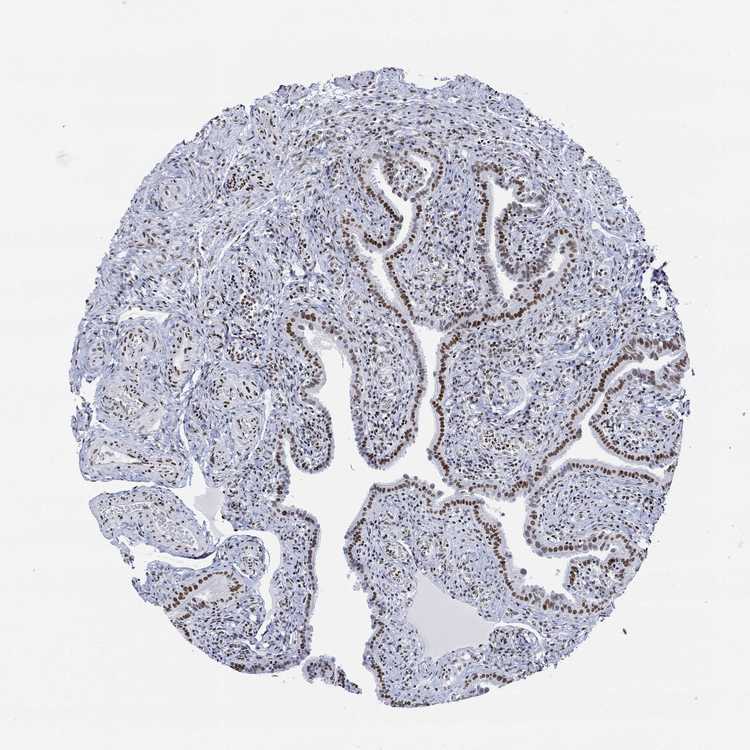

FALLOPIAN TUBE - Antibody stainingi

Antibody staining in the annotated cell types in the current human tissue is reported as not detected, low, medium, or high, based on conventional immunohistochemistry profiling in selected tissues. This score is based on the combination of the staining intensity and fraction of stained cells.

Each image is clickable and will lead to virtual microscopy that enables deeper exploration of all samples and also displays staining intensity scores, fraction scores and subcellular localization as well as patient and tissue information for each sample.

Antibody HPA068431Antibody CAB012235

Glandular cells HighHigh